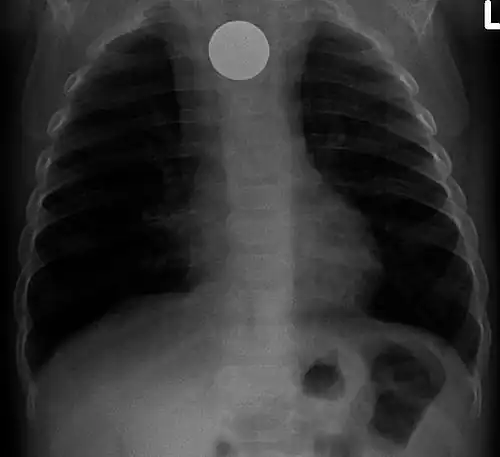

Chest radiograph showing a Venezuelan 25 cent coin lodged in the upper esophagus of a 9-year-old girl. -

A coin seen on AP CXR in the esophagus -

A coin seen on lateral CXR in the esophagus -